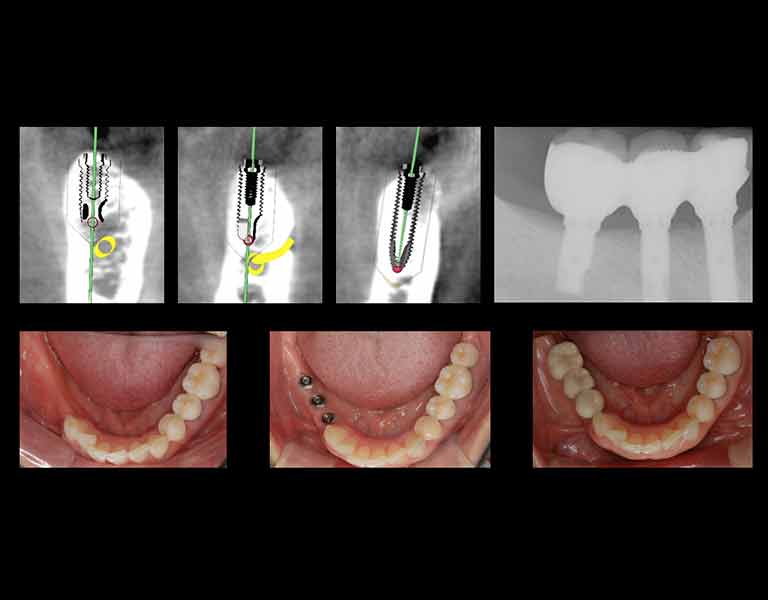

こたに歯科クリニックは開業当初より、インプラント手術をコンスタントに行っています。

図は2007年~2024年のインプラント手術症例総数と成功率です。豊富なインプラント治療経験を基に、安全で確実な治療と患者様に納得していただけるまでご説明することを心がけております。

当院では、一般的な歯科医院では行っていないような、インプラントの難症例と呼ばれるインプラントも数多く行っており、安全性・確実性が非常に高いデジタルインプラントも行なっていますので、通常ではインプラント治療が難しいと言われる持病のある方でもインプラントが受けられる可能性が高くなります。

当院では、骨が少なくて他院でインプラント手術を断られた方でも、骨が少なくてもインプラントが行える技術や、骨を増やしてインプラント手術をする方法、など様々な選択肢から患者様にとって最適な治療をお選びいただくことができます。